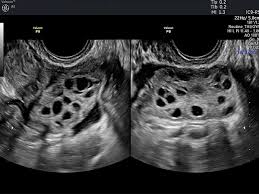

③ 다낭성 난소

초음파에서 난소에 지름 2~9mm의 난포가 12개 이상 관찰되거나, 난소의 크기가 10ml 이상인 경우

기초 혈액검사(호르몬, 혈당, 인슐린 수치 등)와 함께 복부 또는 질식 초음파 검사를 병행합니다.